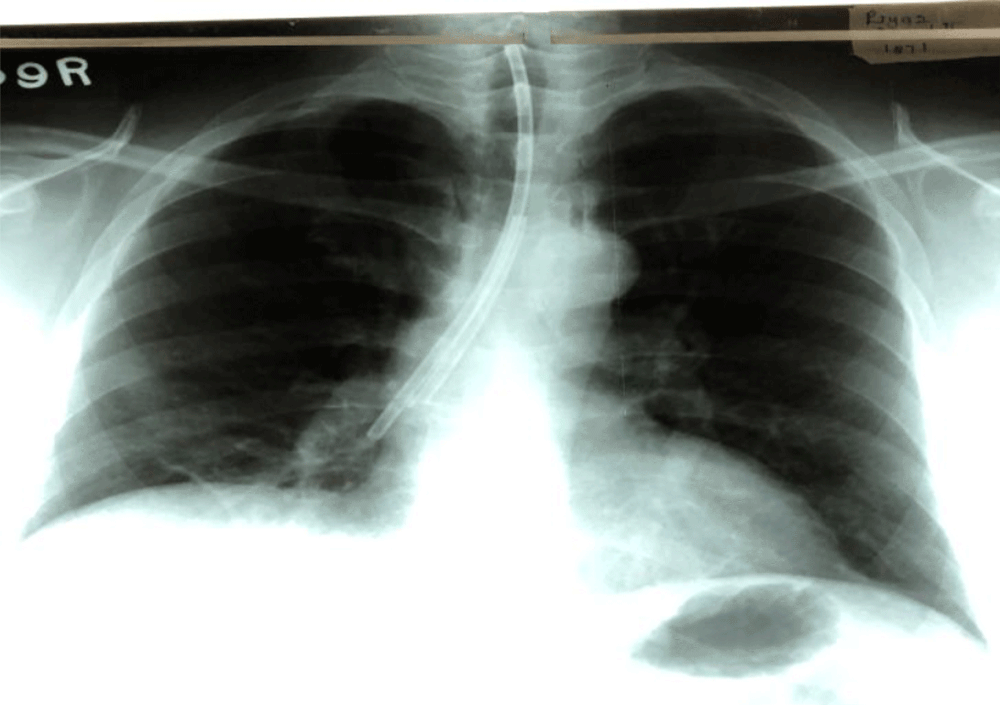

An unusual case of a tracheobronchial foreign body

Jayathilaka .S1 W.H.R de Silva2, Dayasena R.P2 and P.T.P Gunarathna1

We herein report a case of an unusual tracheal foreign body in a 42 year old patient who after having undergone surgery for a tongue base malignancy presented following discharge with progressively worsened intractable cough.